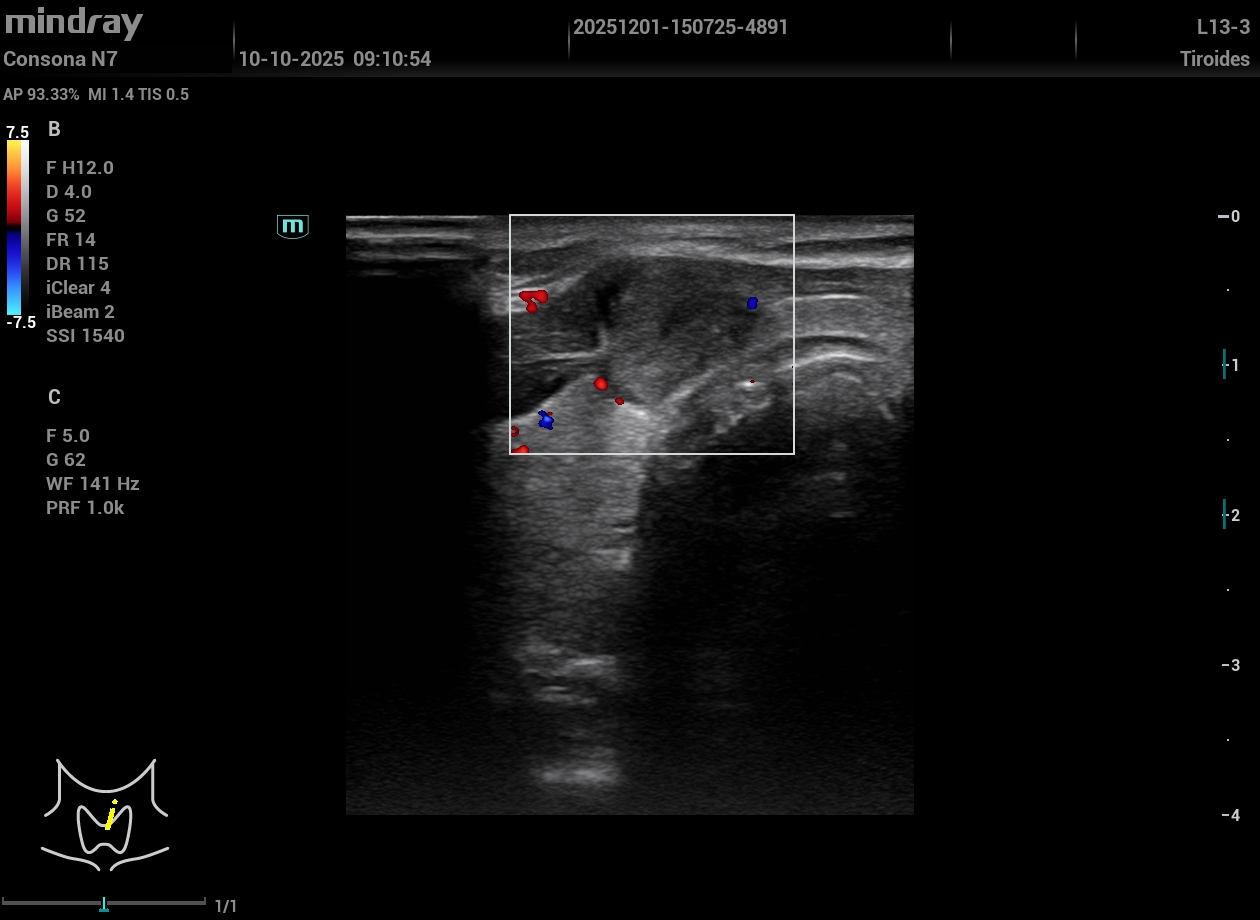

Exploración Física: Nódulo visible y palpable en línea media cervical anterior a la altura de la glándula tiroidea, no doloroso. Tras la exploración manual y dada la reciente aparición del nódulo realizamos ecografía en el momento.

Exploración ecográfica. Se observa un tiroides de tamaño y ecogenicidad normal y en istmo un nódulo hipoecogénico de aspecto heterogéneo, lobulado de bordes parcialmente delimitados, que se extiende fuera de la glándula, DE 14,3 mm de eje mayor, vascularizado y aspecto ecográfico sospechoso. TIRADS 5.

No se aprecian adenopatías patológicas.